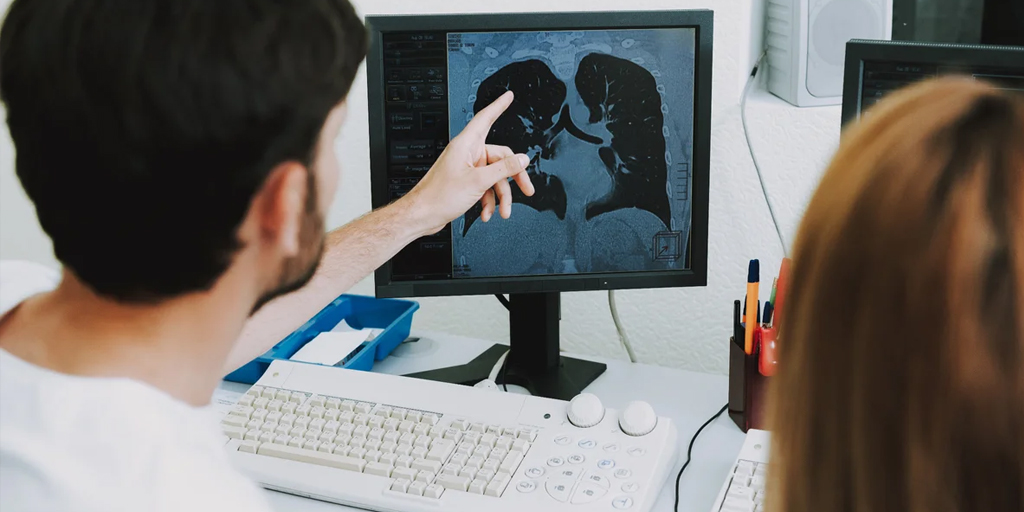

Having a universal record of the user, where you can find in one location current health status and other data such as allergies, medical conditions, symptoms can help a physician around the world heal such patient in a more efficient, objective and with better results, and less duplicated diagnostic studies.

The most important thing is to speed up the work flow with diagnosis imaging, since it is easier to navigate through details that would not identifiable at plain sight gives openness to manage and evaluate the results with Artificial Intelligence help and the Machine Learning (a branch of AI).